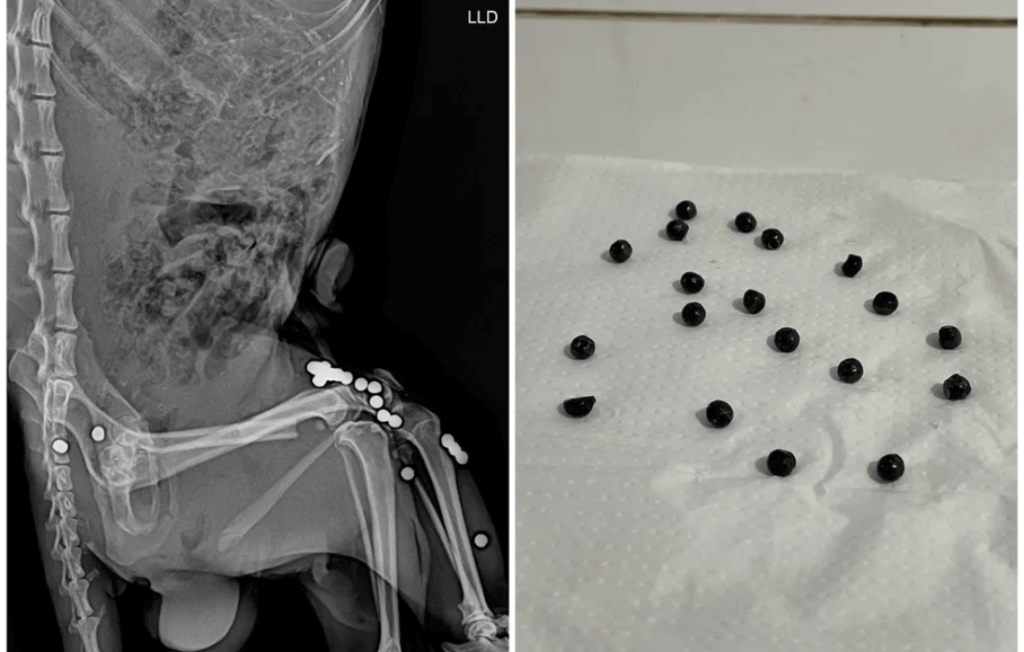

No dia 6 de setembro, uma irara macho foi resgatada na Rodovia Edgard Máximo Zambotto, em Franco da Rocha, após ser atropelada. A equipe da Mata Ciliar encontrou 19 projéteis de arma de chumbo no corpo do animal, que não resistiu aos ferimentos.

“Fizemos a necropsia e, no exame, foi constatado que o animal havia sido vítima de caça com arma de chumbo. Isso com certeza prejudicou a mobilidade dele e contribuiu para o atropelamento e morte,” ressalta Lívia de Oliveira Andrade, médica veterinária patologista da Mata Ciliar.